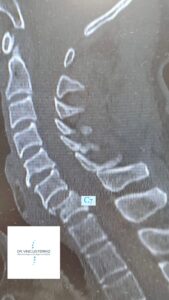

As fraturas tipo A3 e A4 (Burst), ou fraturas em explosão podem ser incompletas (“incomplete burst fractures” – A3) ou completas (“complete burst fractures” – A4). Ambas resultam de mecanismos que provocam altas cargas axiais compressivas, acometendo as regiões anterior e média das vértebras cervicais, geralmente acometem a região da coluna cervical mais baixa (C6 ou C7). As fraturas A3 se caracterizam por lesionarem apenas uma placa terminal (superior ou inferior) e a parede posterior do corpo vertebral, já as fraturas A4 lesionam ambos os platôs vertebrais (superior e inferior) e também a parede posterior do corpo vertebral. Com essa alta carga axial a pressão dentro do disco é rapidamente aumentada, empurrando o platô discal superior para dentro do corpo vertebral, que por sua leva à retropulsão de fragmentos ósseos para dentro do canal vertebral. O córtex posterior do corpo vertebral é lesado, o que promove a diminuição da altura vertebral e, como consequência, gera-se uma postura de cifose segmentar. Mais da metade das fraturas cervicais tipo “burst” podem estar associadas a lesão medular (completa ou incompleta).